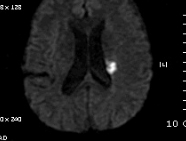

2011-9-10 근력이 G4-  로 지속, 더 이상 나빠지지는 않음. 우측 상지의 움직임이 주과적으로 둔해졌다고 하나 객관적 근력은 정상입니다. Diffusion만 촬영하였습니다.

# 손 o 일 교수님 의견

DWI coronal or saggital view 보면 분명하겠지만 이 사진으로 보니 PCA territory infarction으로 모두 설명되는 것 같습니다. PCA 영역에 hypoperfusion으로 병변이 크지는 것 같습니다. 5-7일 지나야 안정기에 들어갈 것 같습니다.